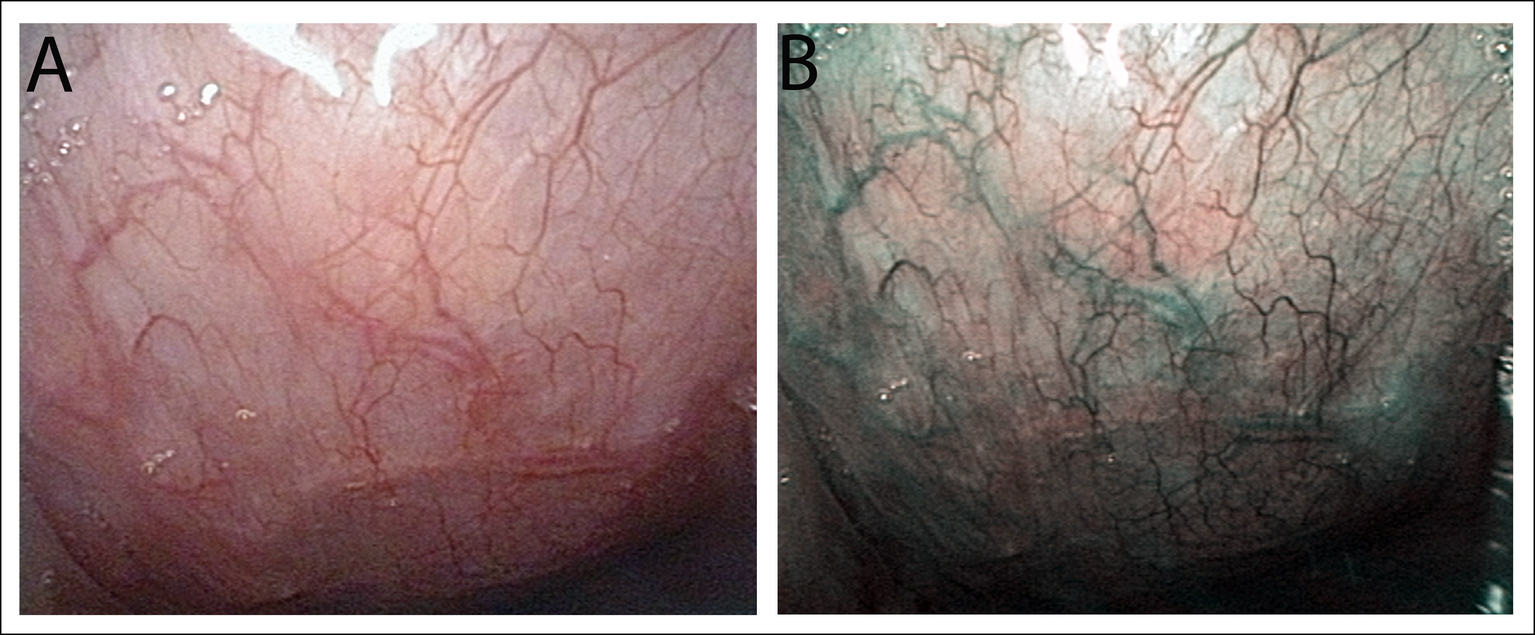

Narrowband imaging (NBI) is one of the most advanced technologies available for endoscopy and related treatments. The NBI light is absorbed by blood vessels and reflected by mucosa. This ensures that stark contrast is observable between the two structures and surface as well as deeply embedded tumors and lesions are clearly visible. Moreover, the visual image of the NBI endoscopy is much clearer than the regular endoscopy making the process more efficient. High Definition (HD) narrow-band imaging endoscopy provides high-quality images in the process. However, magnification endoscopy takes it a step further by magnifying the high-resolution endoscopy images up to 150 times the original image. With the help of NBI-magnifying endoscopy, even the smallest lesions can be detected in the early stages.